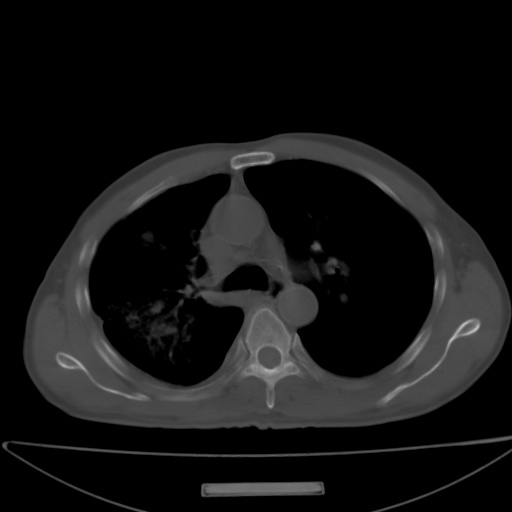

以下是引用jsgdoctor在2008-11-6 22:12:00的发言:[br]右主支气管壁明显增厚,管腔狭窄.考虑为右侧中央型肺癌伴阻塞性炎症\\肺脓肿.

以下是引用zjzjr在2008-11-6 20:25:00的发言:[br]中心型肺ca,合并阻塞性肺炎

以下是引用zsl6918在2008-11-6 19:43:00的发言:[br]右侧中心性肺癌(鳞癌)